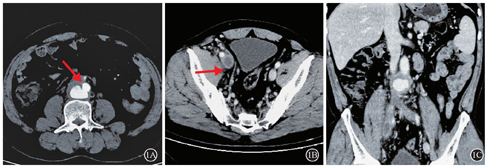

患者,男,51岁,因"反复双下肢水肿7月,右下肢肿胀加重3 d"为主诉入院。患者7月前无明显诱因出现双下肢肿胀,右侧较重,活动及久站后加重,晨起消失。无间歇性跛行及下肢疼痛,未诉腹部及背部疼痛病史。患者至医院行下肢深静脉彩超检查诊断为下肢静脉曲张并给予治疗后,患者症状反复。3 d前患者因"右下肢肿胀加重"至我院就诊。查体:右下肢肿胀,伴小腿胫前色素沉着,范围约6 cm×4 cm。彩超提示:右侧髂总静脉、髂外静脉、股总静脉上段血栓形成,腹主动脉瘤合并血栓形成。上腹部增强CT可见:腹主动脉下段局部管壁见小破口出血,周围组织包裹,血肿形成(图1A),下腔静脉、右侧髂总静脉、髂外静脉及股静脉上段可见充盈缺损影(图1B)。冠状位重建图像(图1C)显示腹主动脉的假性动脉瘤压迫下腔静脉,导致下腔静脉狭窄(图2A)。诊断明确后,行腹主动脉瘤腔内隔绝术(图2),术后3 d拟定行"下腔静脉造影并下肢静脉血栓清除术",术中造影可见下腔静脉下段闭塞,大量侧支循环形成(图3),开通困难。遂术后予以利伐沙班20 mg QD抗凝治疗。

1A:腹主动脉下段局部管壁见小破口出血,周围组织包裹,血肿形成;1B:右侧髂总静脉、髂外静脉及股静脉上段可见充盈缺损影;1C:冠状位重建图像显示腹主动脉近髂动脉分叉处假性动脉瘤(52 mm×43 mm)压迫下腔静脉,导致下腔静脉闭塞。